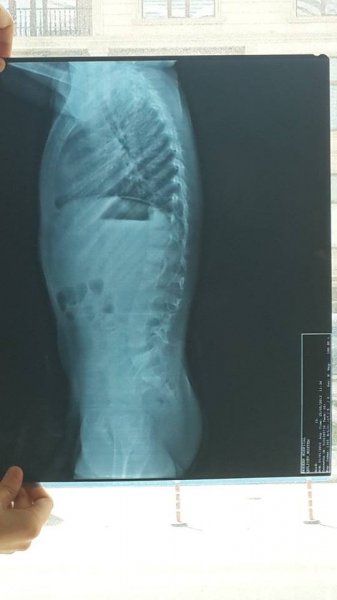

Doğma Sumqayıt şəhərimizin sakini Quliyev Rüstəm Toğrul oğluna anadan gəlmə "Onurğa sütunun döş-bel sahəsində əlavə fəqərə (13cü!) 3-cü dərəcə L1 fəqərə cisminin pazvari deformasiyası, L5 fəqərə cisminin natamam sakralizasiyası, Lomber vertebraların skoliozu " diaqnozu qoyulmuşdur. Xəstəlik nəticəsində 6 yaşlı Rüstəm həmyaşıdları ilə birgə qaça, dura və hətta otura bilmir! Həkimlər ona yalnız və yalnız arxa üstə uzanmağa icazə verir. Normal hamı kimi hərəkət etməsi üçün Rüstəmin kongenital skolioz üçün cərrahi əməliyyat olunmasına ehtiyac görülür. Əməliyyat üçün 22 min avro pul tələb olunur. Bu günədək 11 min avro yığılmışdır. Əziz dostlar, yolun tən yarısındayıq. Rüstəmin öz yaşıdlarından geri qalmaması, onun tezliklə rahat şəkildə hərəkət edə bilməsi üçün Bizlərin yardımına ehtiyacı var.